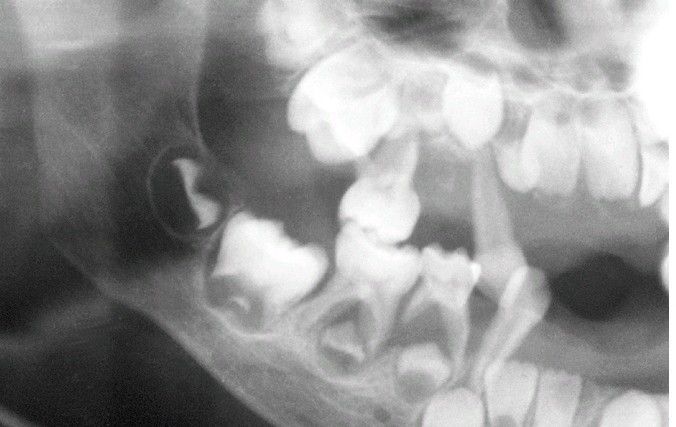

Cyclic neutropenia is one of several conditions that may produce premature bone loss, as shown in the interradicular regions of the mandibular deciduous molar teeth.